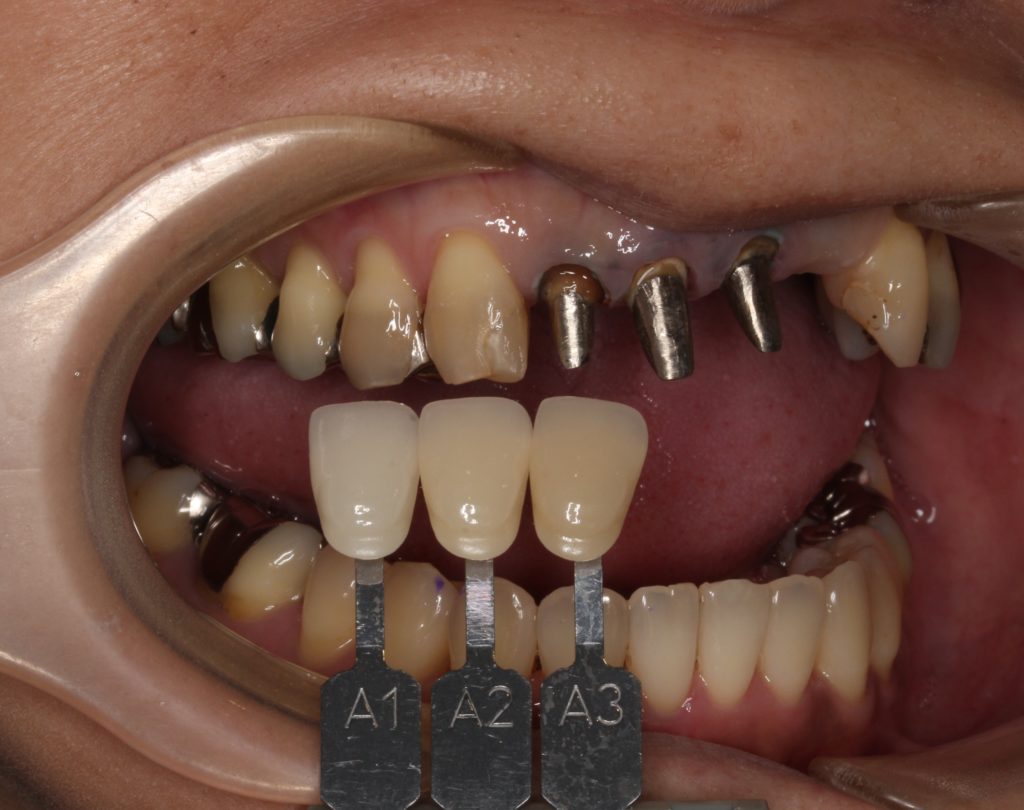

かぶせ物は削って外してしまいます。

このような状態です。

金属の支柱(コア)がしっかりと入っています。

新しいかぶせ物が入るように形を整えます。

歯の色見本で、周囲の歯の色に合わせます。

人それぞれ歯の色が違います。指紋のようなものですね。

また歯の場所によっても色は違い、1本1本グラデーションが出ていています。

下の歯の色も参考にします。

お口の中、前歯の色味のバランスを考えて合わせていきます。